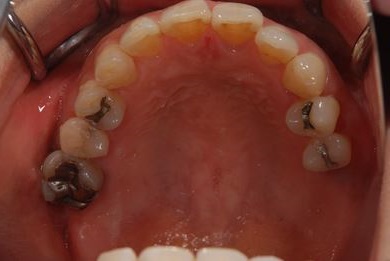

骨再生インプラント治療+セラミック治療+歯肉歯槽骨整形

| 性別/年齢 | 女性 / 42歳 | ||||||||||||||||||||||||||||||||

| 主訴 | インプラント治療を受けたい。 | ||||||||||||||||||||||||||||||||

| 治療方針 | 左上奥欠損部分をインプラント治療にて機能的・審美的回復を行う。 | ||||||||||||||||||||||||||||||||

| 治療内容 | インプラント2本(ソケットリフト)、メタルボンドセラミック3本(メタルボンド用土台1本)、歯肉歯槽骨整形 | ||||||||||||||||||||||||||||||||

| 総治療費 | 1,227,713円 | ||||||||||||||||||||||||||||||||

| 治療期間 | 11ヶ月 |